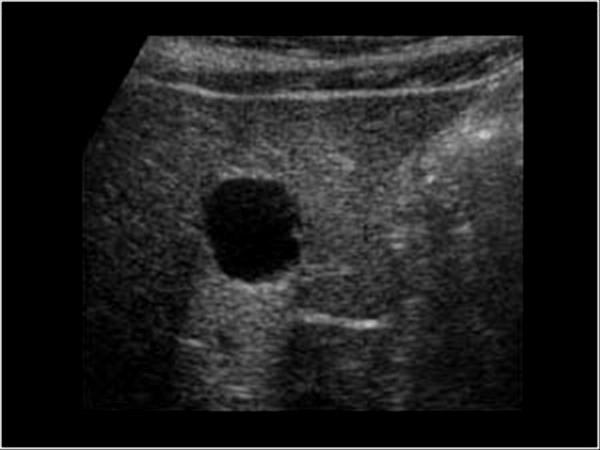

Pancreatic Psydocyst

Spherical fluid collection of pancreatic enzymes that arise from inflamatory, necrotic and hemorrhage processes of the pancrreas

persistently elevated amylase and lipase

Pancreatic Psydocyst

Spherical fluid collection of pancreatic enzymes that arise from inflamatory, necrotic and hemorrhage processes of the pancrreas

persistently elevated amylase and lipase

Pancreatic Psydocyst

Spherical fluid collection of pancreatic enzymes that arise from inflamatory, necrotic and hemorrhage processes of the pancrreas